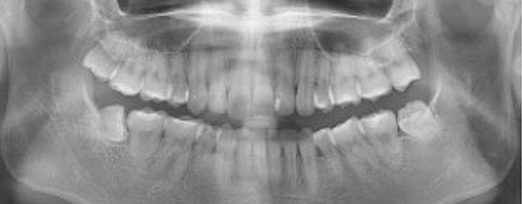

충치치료는 정확하고 객관적인 진단이 가장 중요하며, 충치의 진행단계별로 적합한 치료를 진행해야 합니다.

충치가 있다는 말과 충치치료를 해야한다는 말이 같은 뜻은 아닙니다. 까맣게 보인다고해서 무조건 제거하고 떼워야하는 것은 아닙니다.

초기 충치의 경우 충치를 제거하기보다 그 충치가 더 진행되지 않게 예방하는 것이 더 중요하며, 이는 자연치아를 최대한 보존하고 불필요한 치료를 방지하는 방법입니다. 이를 위해서는 객관적이고 정확하게 충치의 단계를 진단하는 것이 필수적입니다.

청담네오플란트에서는 전문의료진들이 첨단 의료장비와 객관적인 시각자료를 통해 충치의 단계를 정확하게 진단하여 환자분들께 자세한 설명을 드린 후 단계 별로 꼭 필요한 치료만을 진행하고 있습니다.